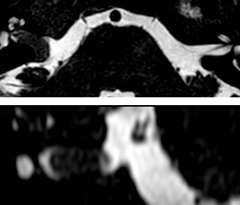

Giant cell arteritis

The 3D TSE T1w black blood MSDE sequence with fat suppression has an isotropic 0.8 mm voxel size and sagittal oblique and axial reformats are made. The images show superficial temporal artery thickening and peri-arterial fat infiltration. The 3D TSE PDw black blood MSDE with fat suppression has 0.55 mm isotropic voxels. The images shows focal involvement of the frontal branch of the superficial temporal artery.

3D TSE T1w BB MSDE

3D TSE PDw BB MSDE